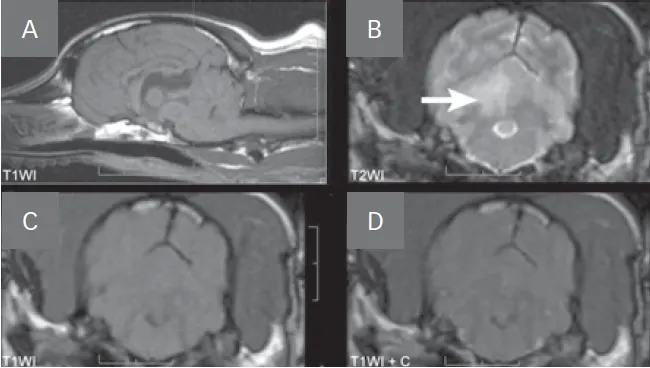

• The MRI appearance of hemorrhagic infarction (Figure 3, see image gallery below) varies greatly as blood cells and hemoglobin degrade (Table 2).

• Hemorrhagic infarcts can be difficult to distinguish from hemorrhagic brain tumors (eg, glioma, hemangiosarcoma).

• The T2*-gradient echo (T2*GRE) sequence is best for identifying hemorrhage as it is hypointense on this sequence.

• T2*GRE is also hypointense for mineralization, air, iron, melanin, and foreign bodies.